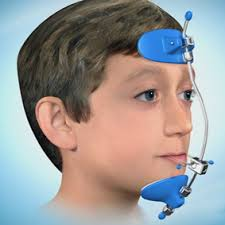

.Underbite

.Underbite

Appliances: Reverse headgear • Braces(prob seen ths on tt but here u go)

Timeline: 9–12 months correction + 12–24 months braces

Timeline: 9–12 months correction + 12–24 months braces

DHC: 4–5

AC: 7–10

Eligibility: Very high

Looks impact: Jaw lines up better / profile looks more even /face symmetry improves(not tht face symmetry even matters)/midface acsends

.Underbite

.UnderbiteAppliances: Reverse headgear • Braces(prob seen ths on tt but here u go)

DHC: 4–5

AC: 7–10

Eligibility: Very high

Looks impact: Jaw lines up better / profile looks more even /face symmetry improves(not tht face symmetry even matters)/midface acsends